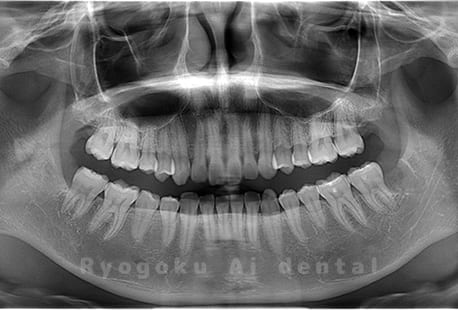

Case02

- 原因

- 下顎の水平埋伏智歯

- 治療内容

- 下顎の水平埋伏智歯を抜歯

<リスク・副作用>

手術後は痛み、腫れ、痺れなどの副作用が生じる場合があります。